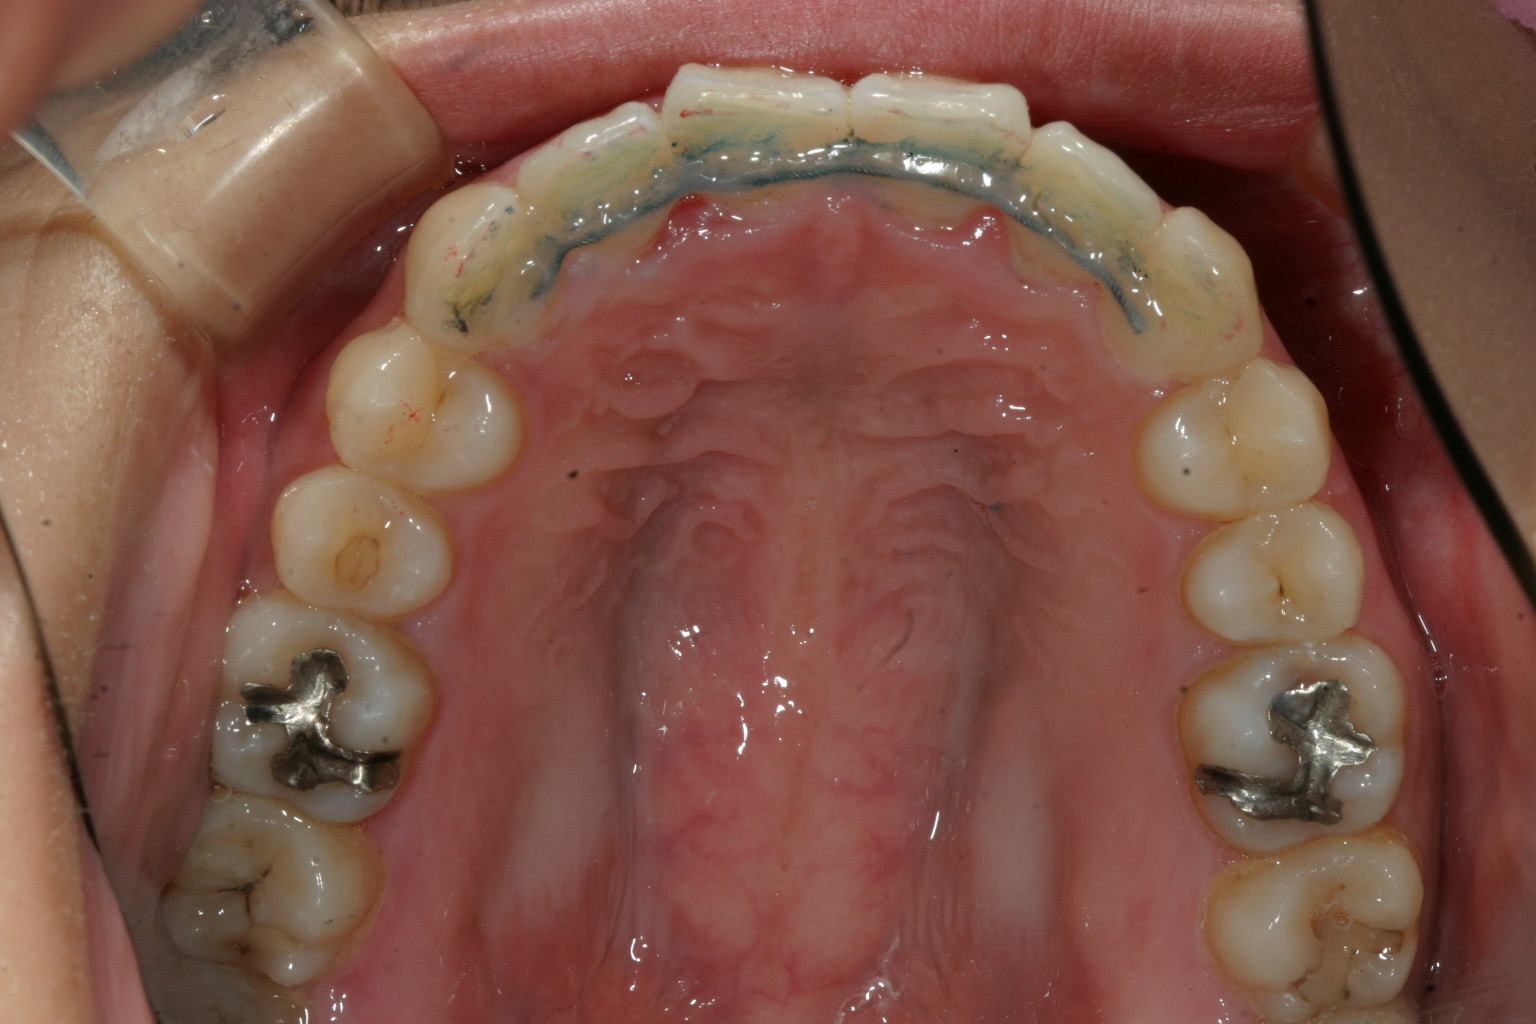

かなりキツイ翼状捻転です。犬歯間幅径が狭いです。

二番目が入っている為少し出加減が気になります。

典型的な犬歯間幅径が狭い為の叢生(翼状捻転)です。

犬歯間を広げることで簡単に改善出来ます。

かなりひどい叢生に見えるのですが治療期間を見てお分かり頂けますように、さほど難症例では有りません。